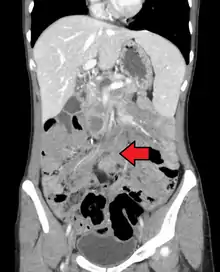

Desmoid tumor as seen on CT scan

MRI or CT imaging scans are commonly used for monitoring.[45][1]